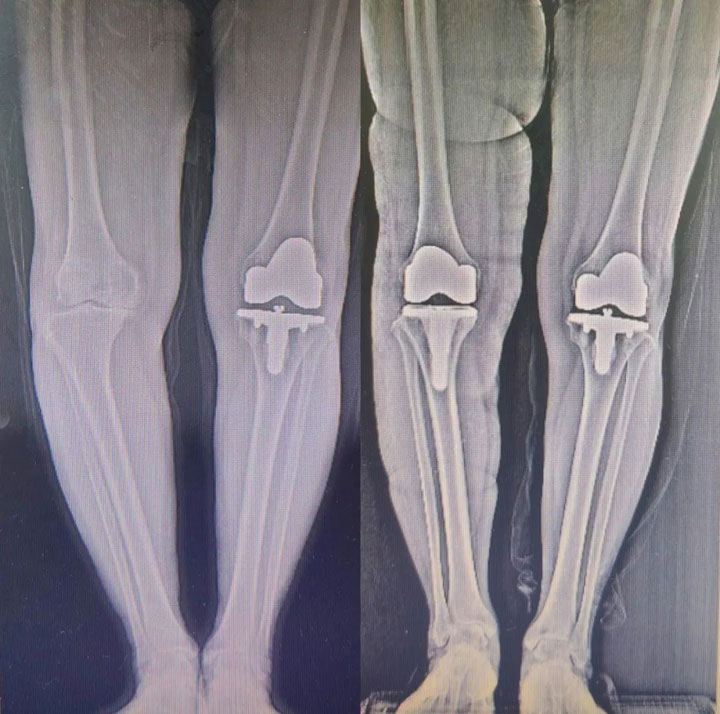

▲术前与术后图

不久,方成院长带领骨科团队在麻醉科和手术室的配合下,顺利为隗奶奶行“右侧全膝关节置换术”。术后第三天,老人就可以借助助行器负重行走了。彻底摆脱了疼痛的折磨,老人说:“这下腿不疼了,终于又能下地(干活)了。”